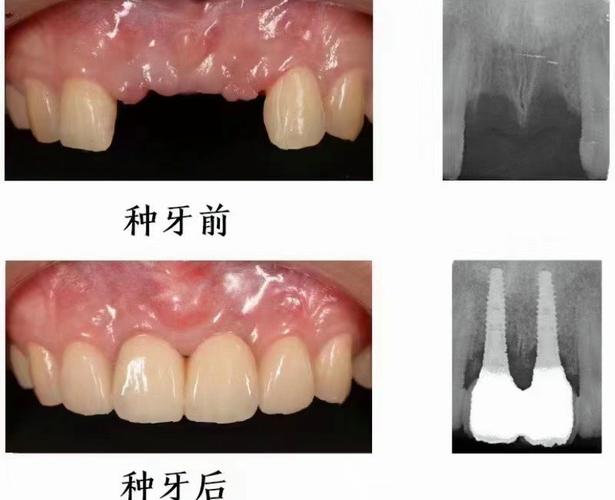

- 骨量充足(≥5mm):若种植体尖端与上颌窦底距离≥2mm,可常规植入种植体,确保初期稳定性即可,无需额外处理。

- 内提升(冲顶术):适用于骨量2-4mm、窦膜完整的情况,在牙槽嵴顶开窗,用专用器械将上颌窦黏膜向上推,植入骨粉(如Bio-Oss),同期或延期植入种植体,创伤小、恢复快,术后1-2周黏膜即可愈合。